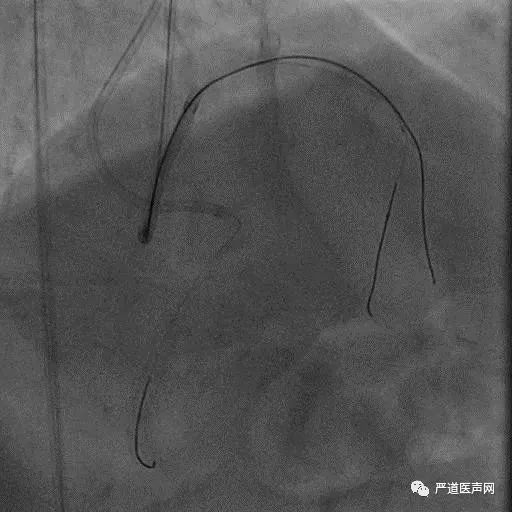

Case 1: Male 66 yrs, first attempt failed in local hospital

7F EBU 3.5, 6F SAL 1.0

• Stump

• Lesion length > 20 mm

• Absence calcification

• Promising landing zone

• Tortuosity epicardial CC

XT R KDL Parallel wiring UB3

Corsair Not Crossboss!

Stingray LP

Stick with GAIA Third

Final Results